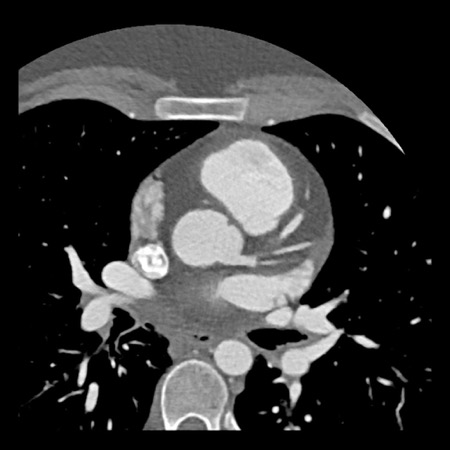

case 1 – CAD-RADS 2/P1

First, scroll through the scan.

Not all images are included. Some images without any abnormalities are skipped

from the series.

How would you describe the findings on the coronary CTA?

The findings are:

- Agatston score of

this patient was 14 (P1). Please, also note the calcification of the aortic valve. - Some partially

calcified and calcified plaques are present in the LAD with mild stenosis

(25-49%). - Calcified-plaque in

the LCX causing minimal stenosis (<25%). - Non-calcified

plaque in the distal RCA causing minimal stenosis (<25%). - This patient classifies

as CAD-RADS 2/P1, which means no further workup is needed.